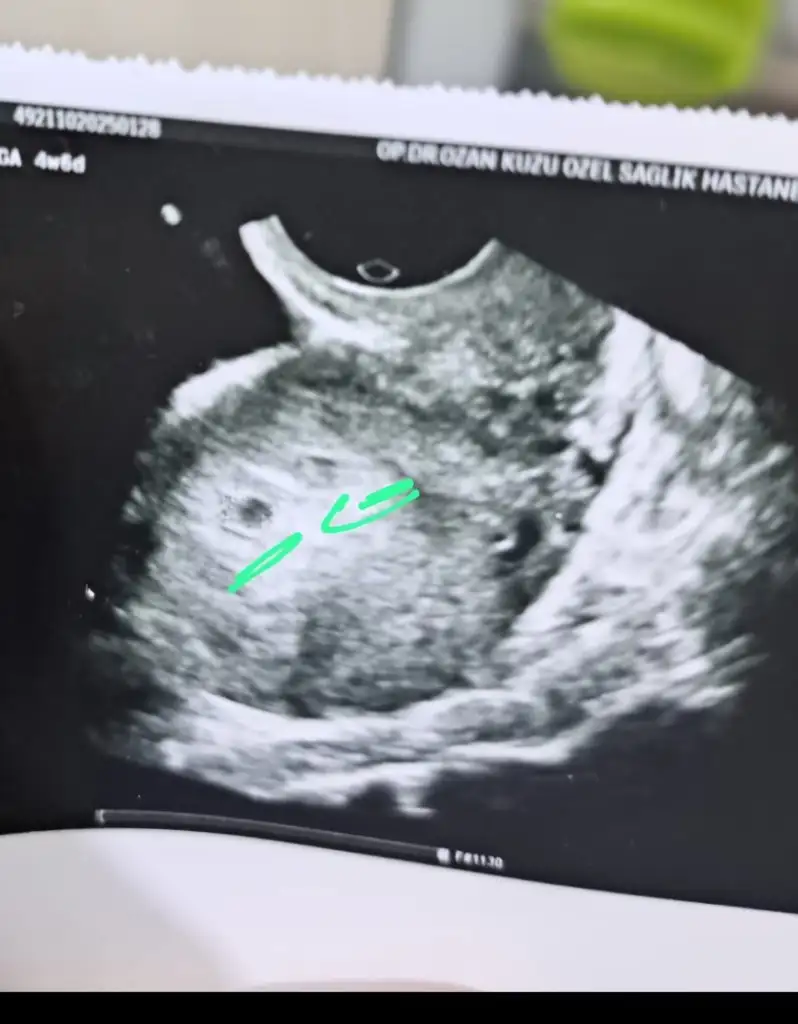

Arkadaşlar merhaba 4+6 da gittim doktora kesemin yanında aynı kese gibi bir tane daha var. İkiz gebelik olabilir mi? Cevaplarınız için şimdiden çok teşekkür ederimayrıca benide gruba ekler misiniz

Hiç anlamam. Ama Dr ne dedi böyle bir ihtimal söyledi mi kalp atışını gördün mü ne zaman çağırdı bir dahakine.

Son adet tarihim 25 Aralık. Yaşım 30. İlk çocuğum. 4 hafta 6 günde keseyi gördük. 1 Ekim doğum tarihi. Kalp atışını yarından sonra dinleyeceğiz

Merhaba kızlar benımde ikinci gebeliğim. İlk kızım 9yasında sat 23aralık ona göre 6/2 ama bugun doktora gittim sadece keseyi gördüm oda vajinal ultrasondan. Kalp atısı bekliyordum. Ikı hafta sonra tekrar gidicem umarım boş değildir. Sürekli bir adet sancısı gibi sancım var Korkuyorum açıkcası. Doktor kese normal rahim iyi durumda dedi.